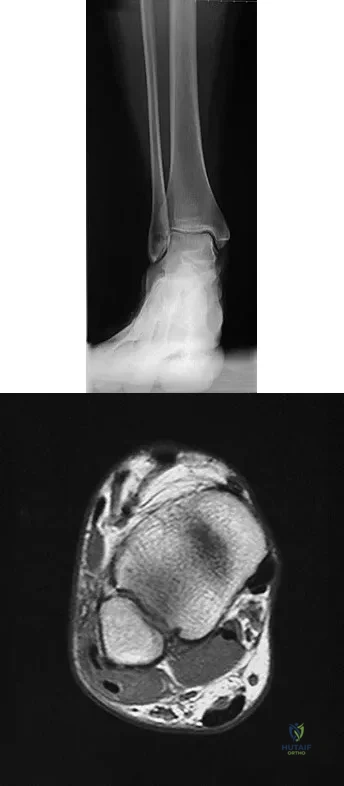

A 25-year-old competitive skier sustains a twisting injury to the right ankle while skiing. She is unable to continue the activity secondary to severe lateral ankle pain. Examination reveals ecchymosis and fullness over the lateral malleolus with pain and weakness on active ankle dorsiflexion and external rotation. There is no medial-sided pain. Neurovascular examination is normal. An AP radiograph and MRI scan are shown in Figures 17a and 17b, respectively. Management should consist of

Explanation